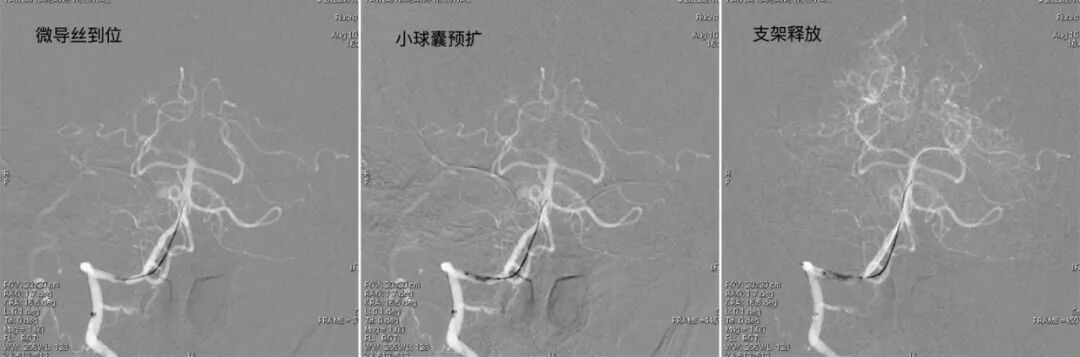

导引导管到位,导丝通过病变。

导丝怎么扩【载药时代 球扩天下】NOVA DES®颅内药物洗脱支架在椎动脉颅内段重度狭窄的应用二例_https://www.jmylbn.com_新闻资讯_第10张

球囊通过病变

导丝怎么扩【载药时代 球扩天下】NOVA DES®颅内药物洗脱支架在椎动脉颅内段重度狭窄的应用二例_https://www.jmylbn.com_新闻资讯_第11张

球囊扩张过程。

导丝怎么扩【载药时代 球扩天下】NOVA DES®颅内药物洗脱支架在椎动脉颅内段重度狭窄的应用二例_https://www.jmylbn.com_新闻资讯_第12张

释放赛诺神畅 颅内药物洗脱支架NOVA DES®尽快到位,防止药物涂层损耗。

导丝怎么扩【载药时代 球扩天下】NOVA DES®颅内药物洗脱支架在椎动脉颅内段重度狭窄的应用二例_https://www.jmylbn.com_新闻资讯_第13张

V4近心端狭窄处接自膨支架,避开小脑后下动脉。

导丝怎么扩【载药时代 球扩天下】NOVA DES®颅内药物洗脱支架在椎动脉颅内段重度狭窄的应用二例_https://www.jmylbn.com_新闻资讯_第14张

两枚支架释放完成。

导丝怎么扩【载药时代 球扩天下】NOVA DES®颅内药物洗脱支架在椎动脉颅内段重度狭窄的应用二例_https://www.jmylbn.com_新闻资讯_第15张